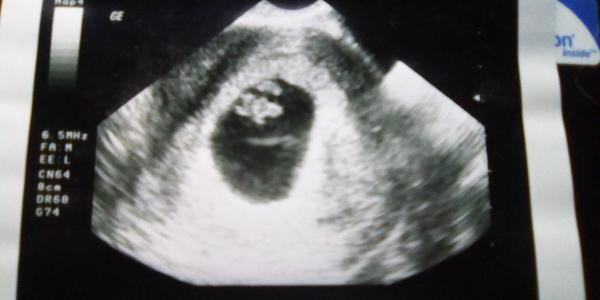

@marcetta_k no, moje doktorka dela utz pro zijsteni zacinajiciho tehotensvi uz v cca 6.tt - to jen potvrdi ze je tam dutinka znacici zacinajici tehu... Rovnou objedna na dalsi kontrolu za 2 tydny (cca na 8tt) aby byla jistota, ze se tehotensvi vyvyji a je videt tlukot srdicka - kdyz je to ok, tak v 10tt odbery a prvni poradna.... U prvni dcerky mi v tom 10tt ultrazvuk nedelala, ale dneska doktorka co tam byla na zaskoku mi ho udelala, tak uz mam i dve fotecky - z minule a z dnesni kontroly 🙂

@lucinkamarecek no, ono asi i zalezi na tom, jak kvalitni ultrazvuk doktor ma... ta moje ma takovy stary, srdicko v 6tt na nem jeste videt neni, jen cerny flek (dutinka) a v nem miniaturni bila carecka (embryjko)... asi proto pak dela dalsi kontrolu v tom 8tt, kdy uz to srdicko je videt krasne...